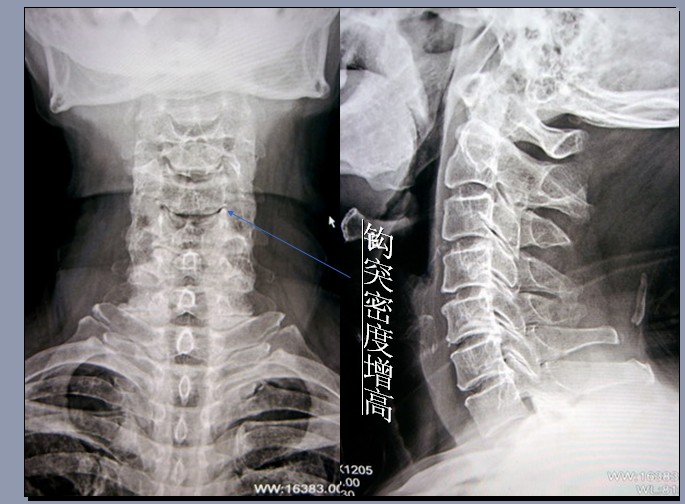

观察椎间隙情况,观察左右钩椎关节是否对称,钩突是否有退变(变尖).

钩椎关节退变容易被脊柱外科医师忽视的结构